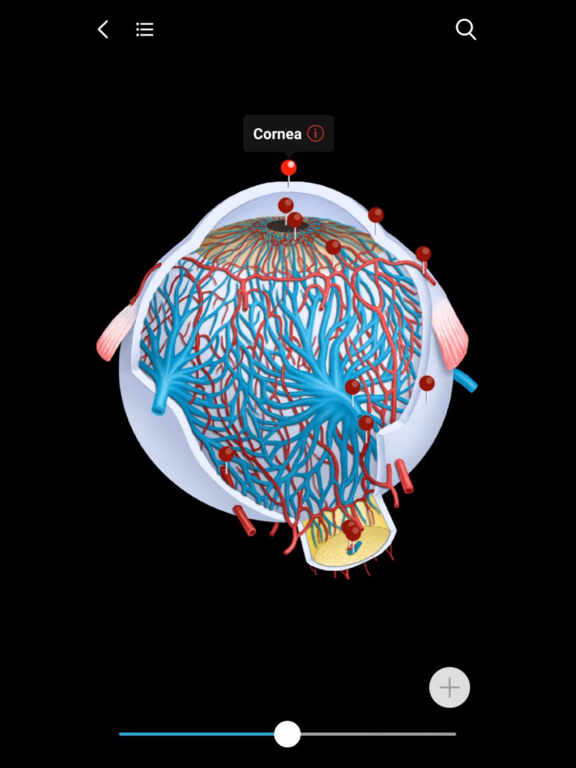

2. MedImaging also includes 3D AR and 2D  anatomy pictures. When you slide to any image in the atlas, you can easily find the 3D and 2D anatomical pictures most relevant to the image. This means that you don't have to go through the anatomy textbooks if you forget the association between the general body anatomy and imaging anatomy. Just one click, you can build the intrinsic association between general anatomy and medical imaging. You'll understand medical imaging more efficiently and easily.

3. Clinically 2D diagrams are also integrated seamlessly into all images in the atlases. For example, cerebrovascular blood supply area, DSA vascular segmentation, cerebral leaf segmentation, liver segmentation, pulmonary leaf segmentation, etc.